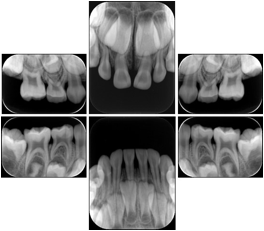

6 Standard Pedodontic A Dental Image Layout

DL-P001A

Reference:

00

Pedodontic

16, 55, 54, 53

01

52, 51, 61, 62

02

63, 64, 65, 26

10

46, 85, 84, 83,

11

82, 81, 71, 72

12

73, 74, 75, 36

6 Standard Pedodontic B Dental Image Layout

DL-P001B